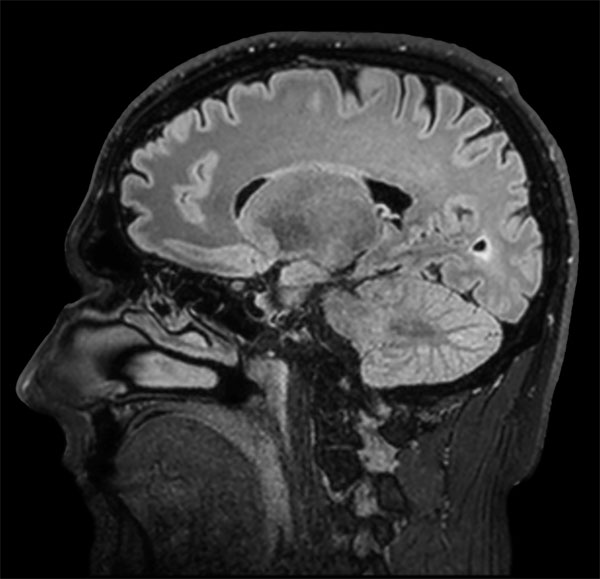

dS SENSE in Brain Imaging

Used Solution

• Clinical Application